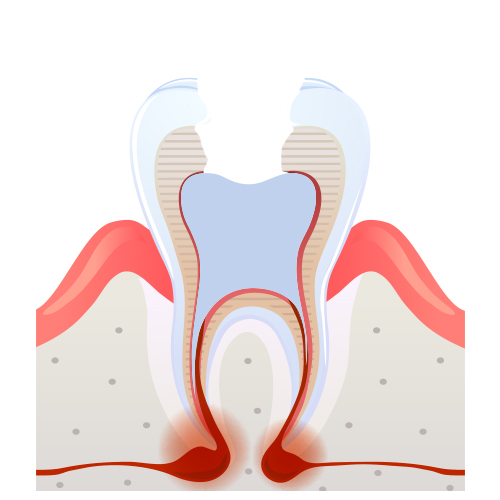

신경치료 과정

02

02

충치제거

03

03

신경제거 및 길이측정

05

05

신경관 영구재료로 채움